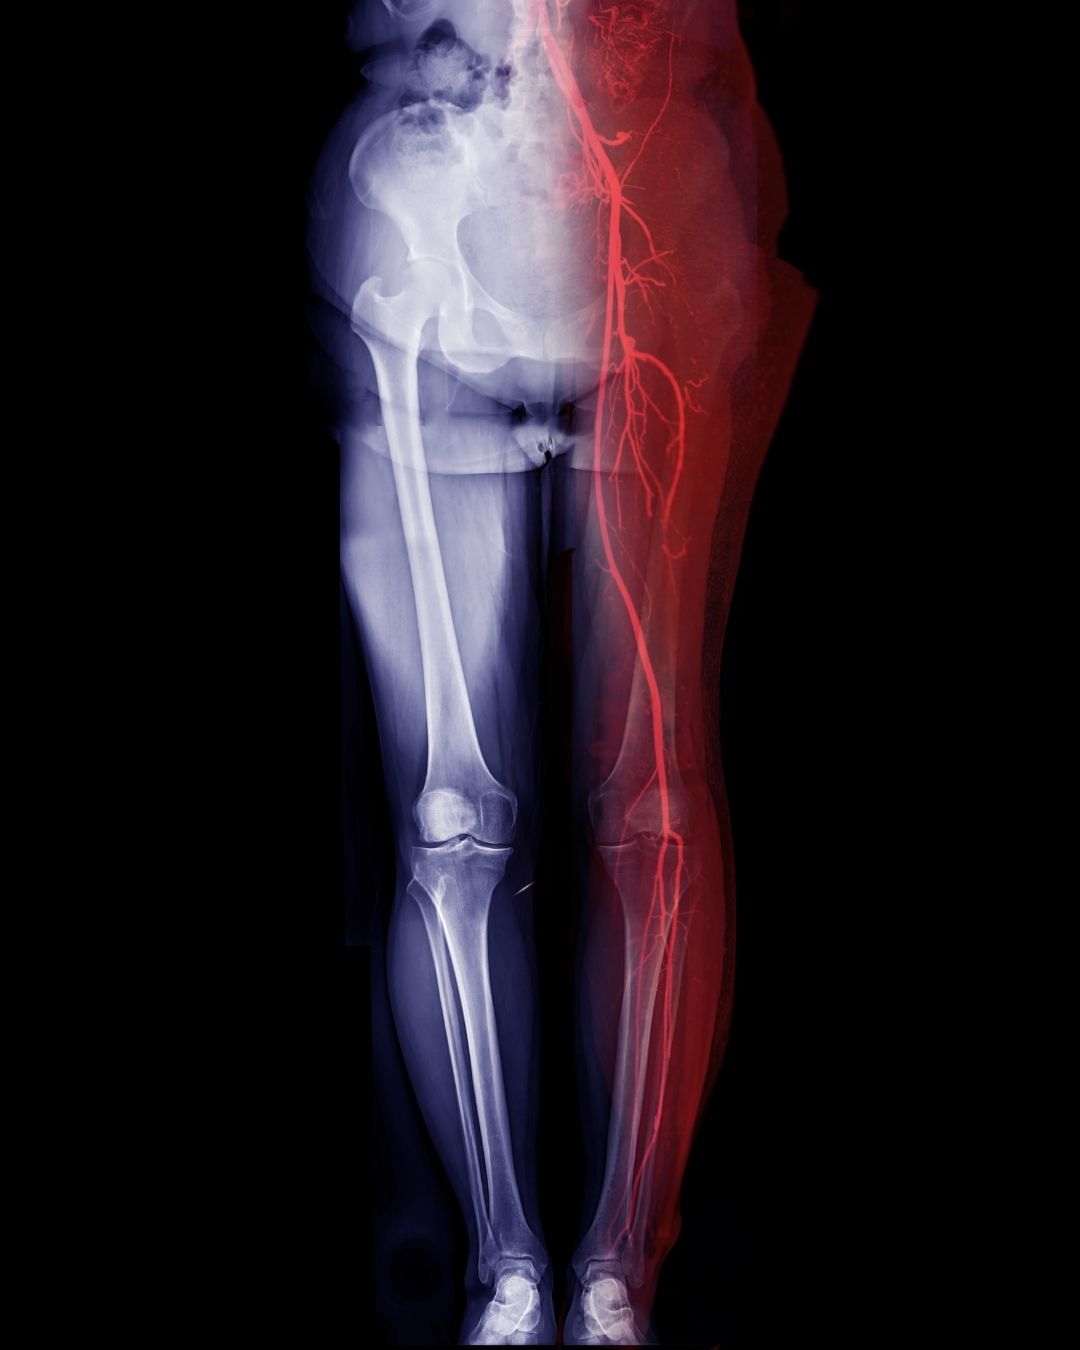

Periferik MR Anjiyo, vücudunuzdaki kol ve bacaklardaki atardamarları ve toplardamarları görüntülemek için yapılan bir manyetik rezonans görüntüleme (MR) yöntemidir. Basitçe söylemek gerekirse, damarlarınızı röntgen benzeri bir şekilde, ancak radyasyon kullanmadan, detaylı olarak gösterir.

1. Amaç: Damar tıkanıklıkları, daralmalar, anevrizmalar veya damar hastalıklarını teşhis etmek.

2. Yöntem: MR cihazı ve bazen kontrast madde kullanılarak damarların detaylı görüntüleri elde edilir.

• Bacaklarda dolaşım sorunları (periferik arter hastalığı)